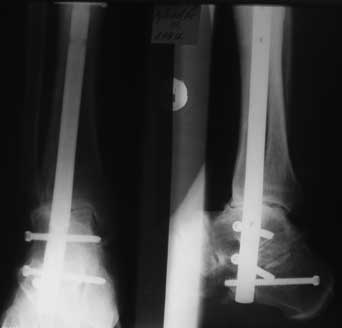

Взаимоисключающие требования, т.к. от боли его из бавит только артродез, но он, соответственно, лишит движений. В приложении - малоинвазивный компрессионный артродез с помощью БИОС. Боли прошли сразу после операции.